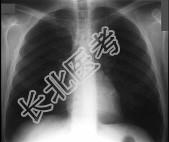

- 单项选择题在哮喘急性发作的病程中患者出现颈部皮下气肿,胸片见图。说明此患者有下列哪一种并发症存在 ( )

A、气胸

B、纵隔气肿

C、间质性肺气肿

D、肺囊肿

E、肺大疱